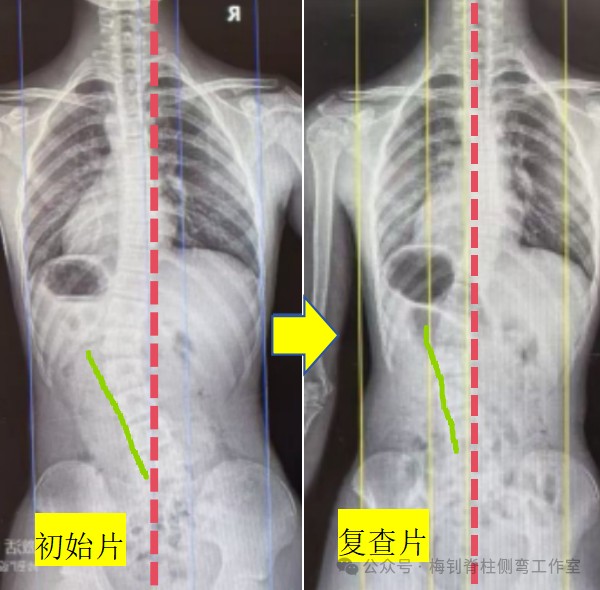

14岁女孩,生长末期,复查拍片后,被骨科医生告知,侧弯加重了,支具不合格,建议更换。家长马上比较忧虑,孩子也急哭了。家长马上把片子发给我们,当看到片子我们放心了:复查片力线明显好转,腰椎下半段明显变直,顶椎偏移程度降低,侧弯度数好转不多,但没有加重,只是医生测量的“加重”,所以,X线片复查结果整体向好。后面孩子来复查,体表的好转也印证了侧弯整体向好的结果。

为了彻底消除家长的顾虑,支具根据现状稍作调整后,再次拍片查看,结果比较理想,家长也彻底放心了。对于该骨科医生的建议,我们不做评论,或许他真的不懂吧~

生长末期,矫正不易,希望孩子重拾信心,最终有好的结果。